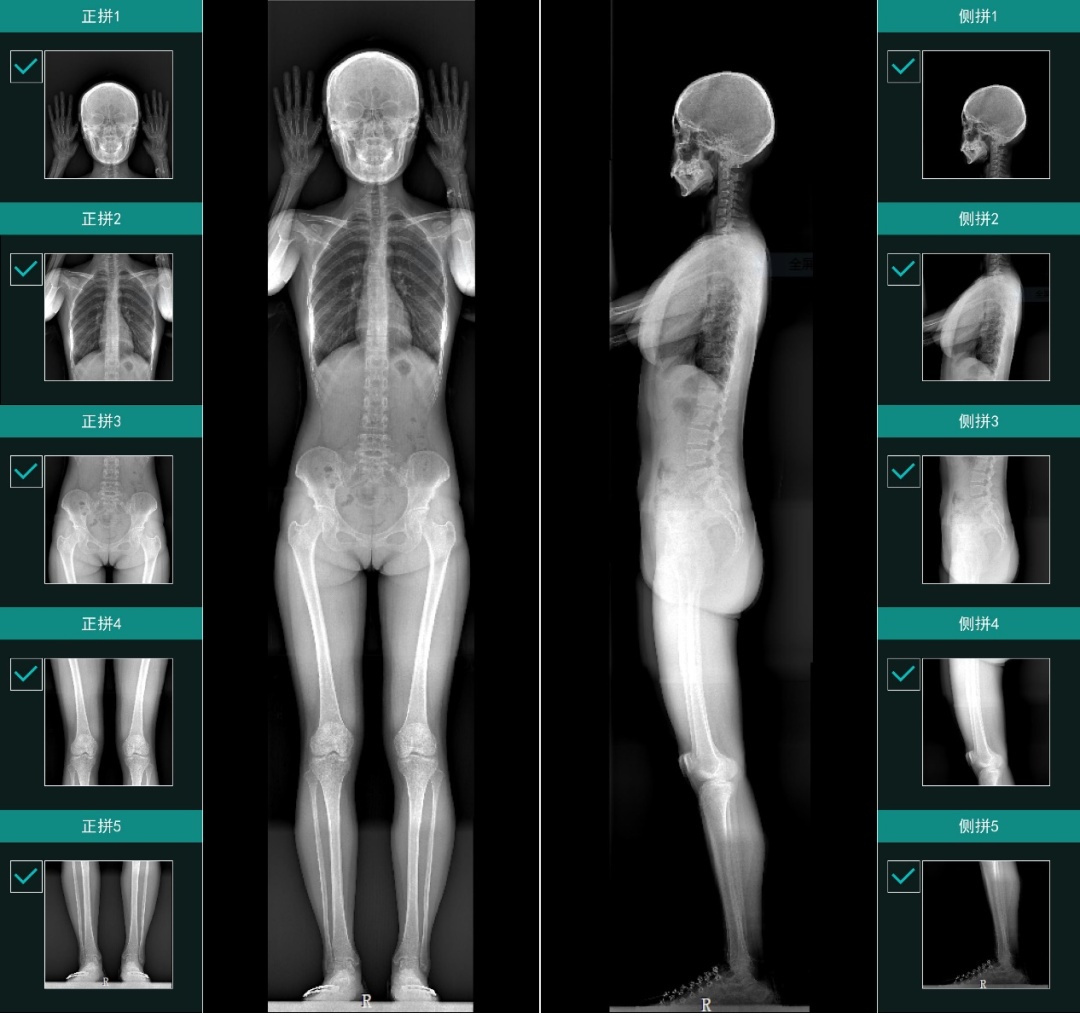

对于骨折、骨裂、骨骼畸形等问题,目前医院里的影像诊疗设备大多能直接显示出来,但对于没有明显结构损伤的运动功能障碍,这些设备往往无从捕捉:传统的影像只能反映结构问题,不能够反映疾病或损伤对运动功能带来实际影响。

“这段话对我的冲击非常大,我第一次清晰地意识到:原来自己做的这个技术这么有意思。”蔡宗远说道。“我们提出来的x射线立体摄影的概念,就是要能够看到骨关节的运动状态,对运动做评价评分,从而去解决现在骨科诊断与治疗上的限制。”蔡宗远介绍道。

2022年7月,由涛影医疗自主研发的全身双平面X射线摄影系统Ti-WISH-IL取得中国医疗器械注册证。截至目前,已有80余家医院签订装机合同,5家医院实现商业装机。